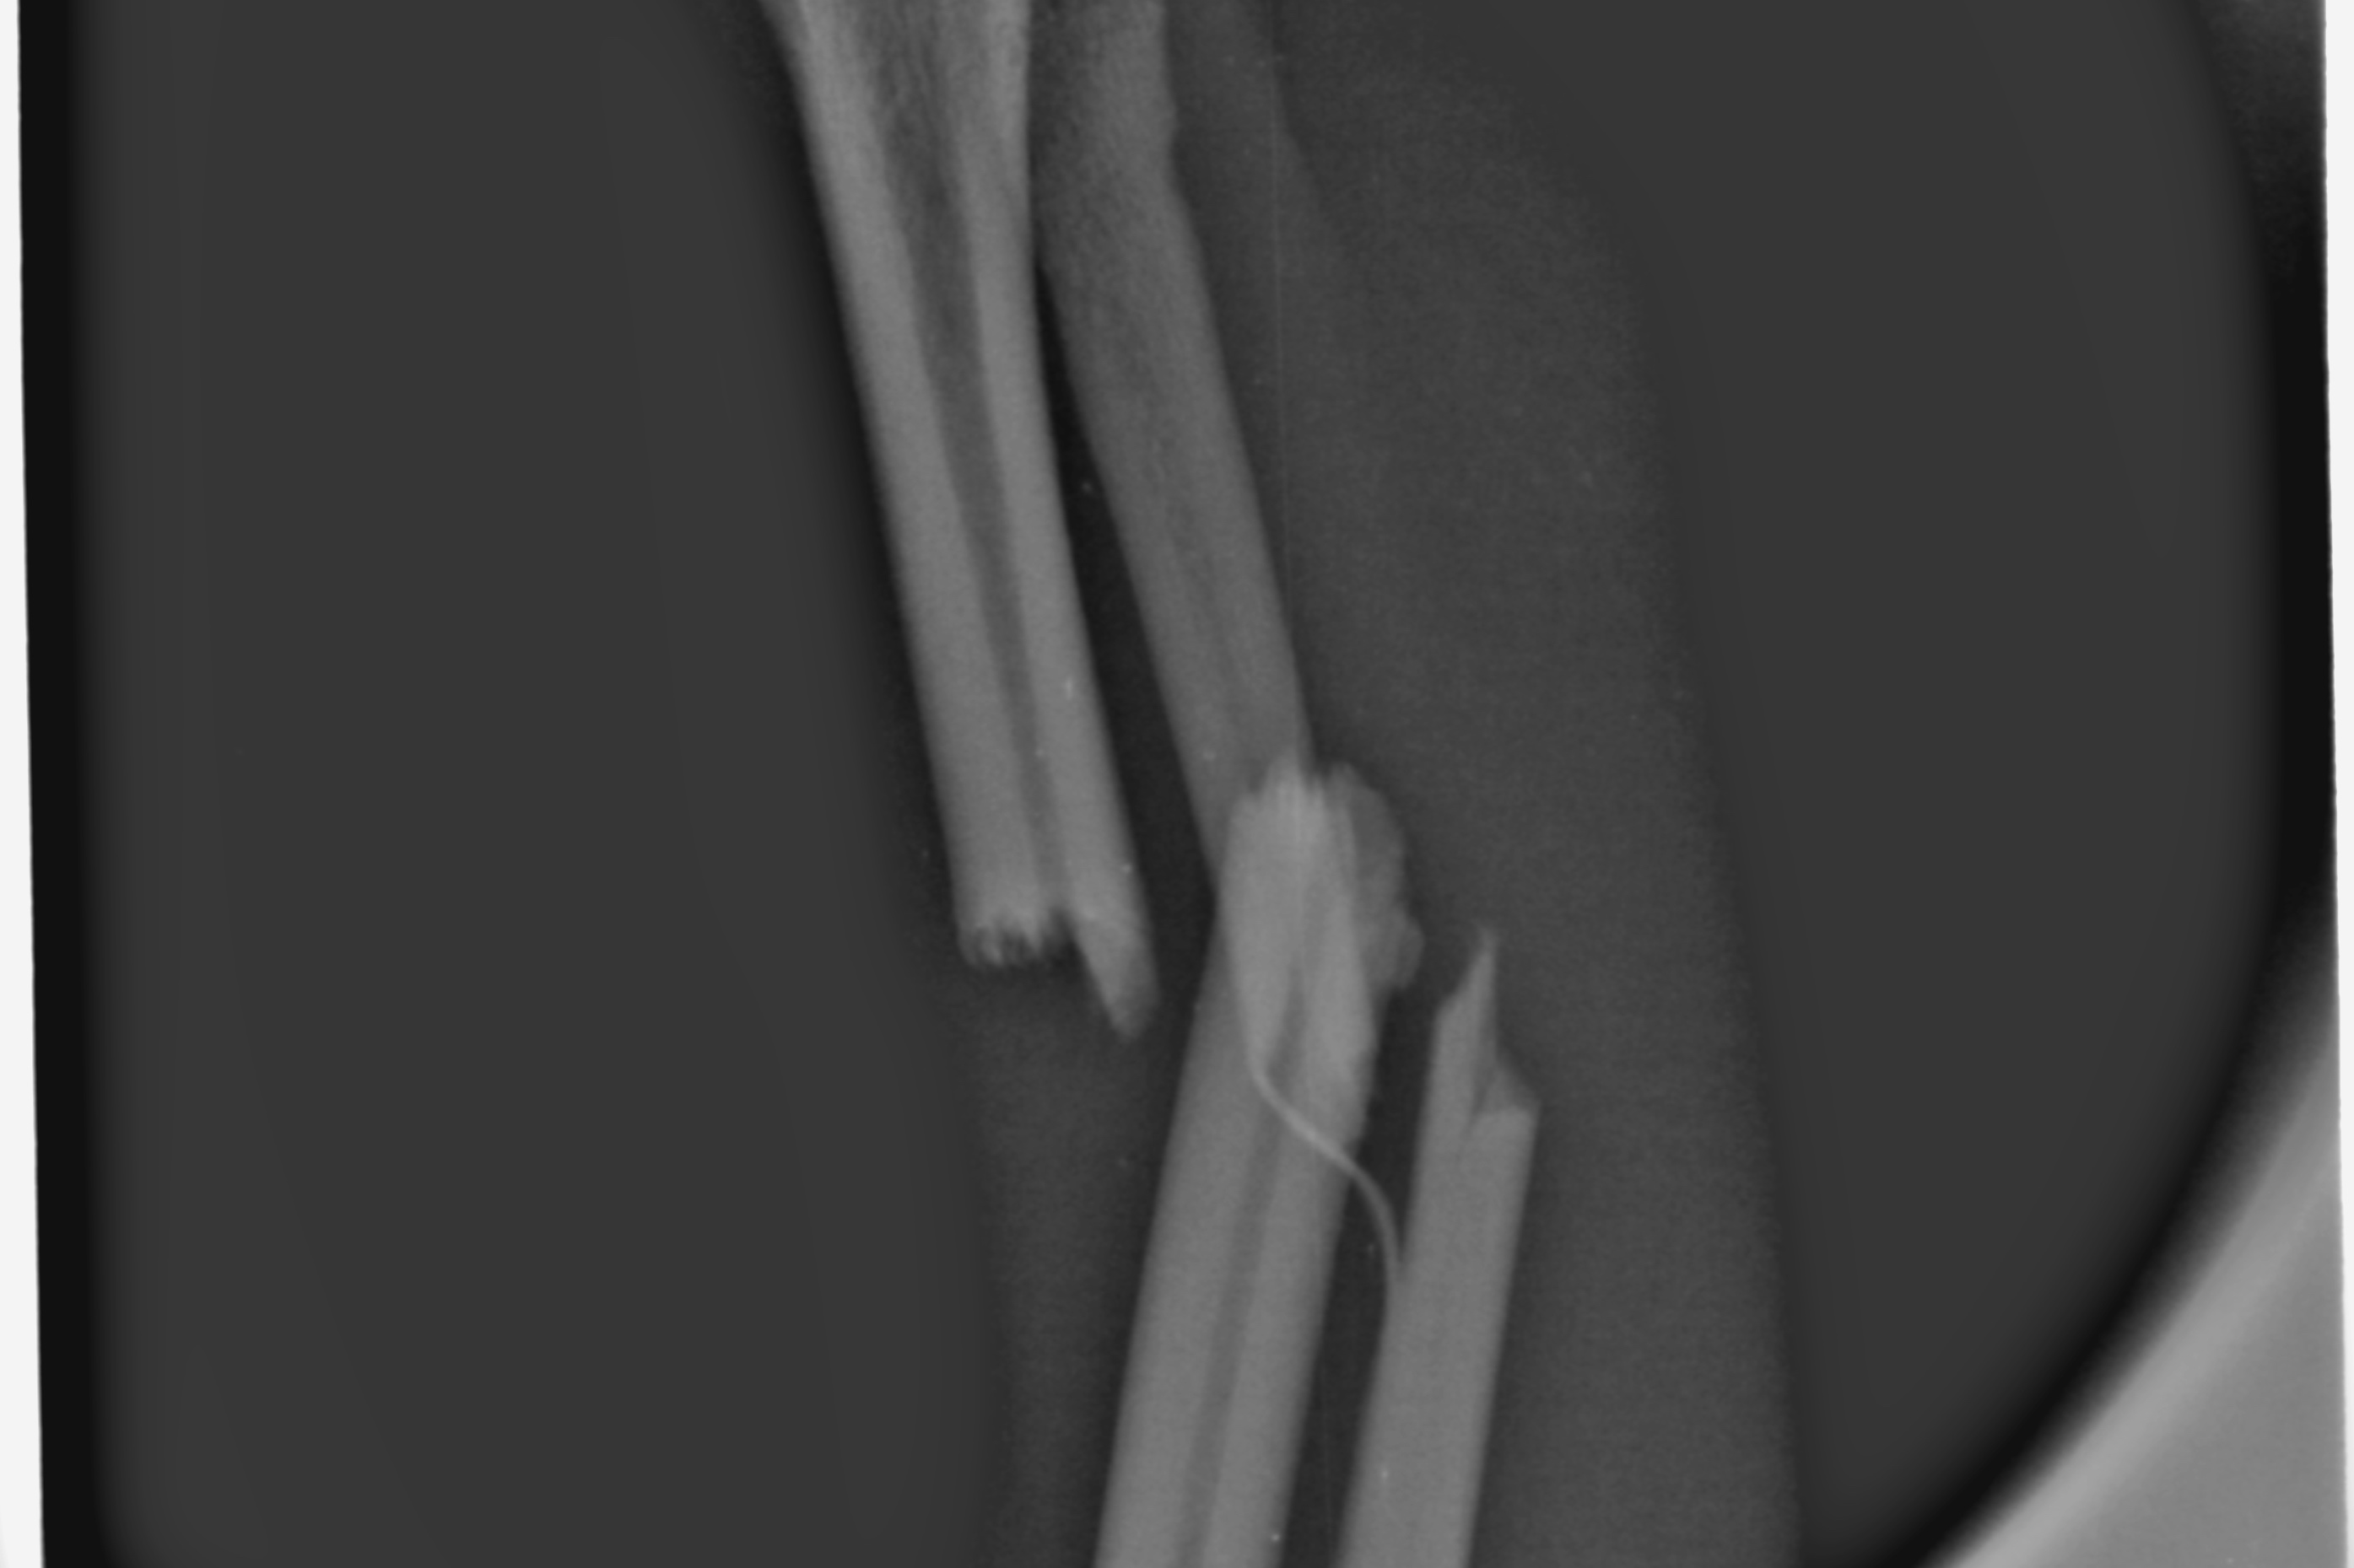

Auf diesen Bildern sehe ich etwas mehr als auf den herkömmlichen chemisch entwickelten Aufnahmen. Die Aufnahmen können vergrößert oder gefiltert werden. Sie lassen sich unkompliziert speichern und verschicken. Der Kunde kann eine Datei mitnehmen; der fachliche Austausch unter Tierärzten wird schneller.

Aber der Clou ist: Die Speicherfolien sind so klein, daß ich damit einen entscheidenden technologischen Vorteil gegenüber meiner alten Technik habe. Ich kann überlagerungsfrei jeden Zahn einzeln darstellen. Ich kann auch Pfötchen und Flügel röntgen, ohne gleich den ganz großen Apparatismus anzuwerfen.

Ein paar Beispielaufnahmen

aus unserer Röntgenpraxis